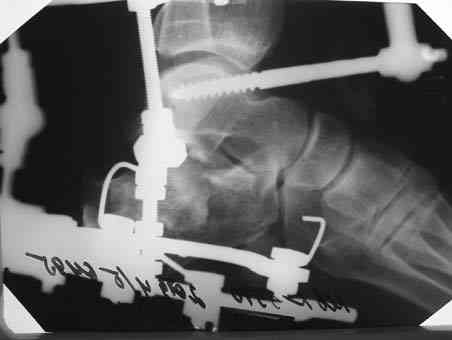

Если примите решение - детали можем обсудить. Во вложении - один из вариантов компоновки.

Альтернатива-КДО. Базовый аппарат из 2х колец в н\3 голени, 2 стержня Шанца по бокам от пяточного бугра до линии перелома, затем используя стержни как рычаги закрытая репозиция и стержни соединяются с базовым аппаратом. На стопе ещё полукольцо и спица ч\з основания плюсневых костей. При успешной репозиции стержни вкручиваются дальше во второй отломок, повышая тем самым жёсткость фиксации.

В Вашей ситуации мы бы выполняли чрескостный остеосинтез обеих пяточных костей.

Первый этап - это репозиция на операционном столе, причем для удобства репозиции со стороны пяточного бугра в косо-сагиттальных плоскости ввели бы 2 консольные короткие спицы. Они были бы и рычагом и органом управления отломками. После предварительной репозиции те же спицы могут быть проведены в таран или прочие кости для временной фиксации. Теперь R-графия и выбор компоновки.

На рисунке стандартная схема, но от ситуации могут быть варианты.